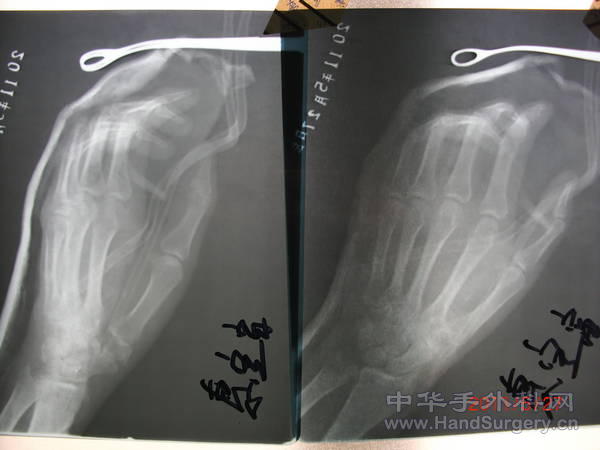

混凝土高压灌注伤

今日拆vsd,豌豆骨游离移植(尺动脉腕上皮支为血管蒂)修复大多角骨缺损,骨间掌侧动脉背侧穿支肌皮瓣修复手背缺损。 CIMG3475.JPG CIMG3476.JPG CIMG3479.JPG CIMG3480.JPG CIMG3481.JPG CIMG3485.JPG CIMG3487.JPG CIMG3495.JPG CIMG3505.JPG

术后15日,皮瓣成活,复查x片豌豆骨游离移植修复大多角骨大部缺损位置良好。